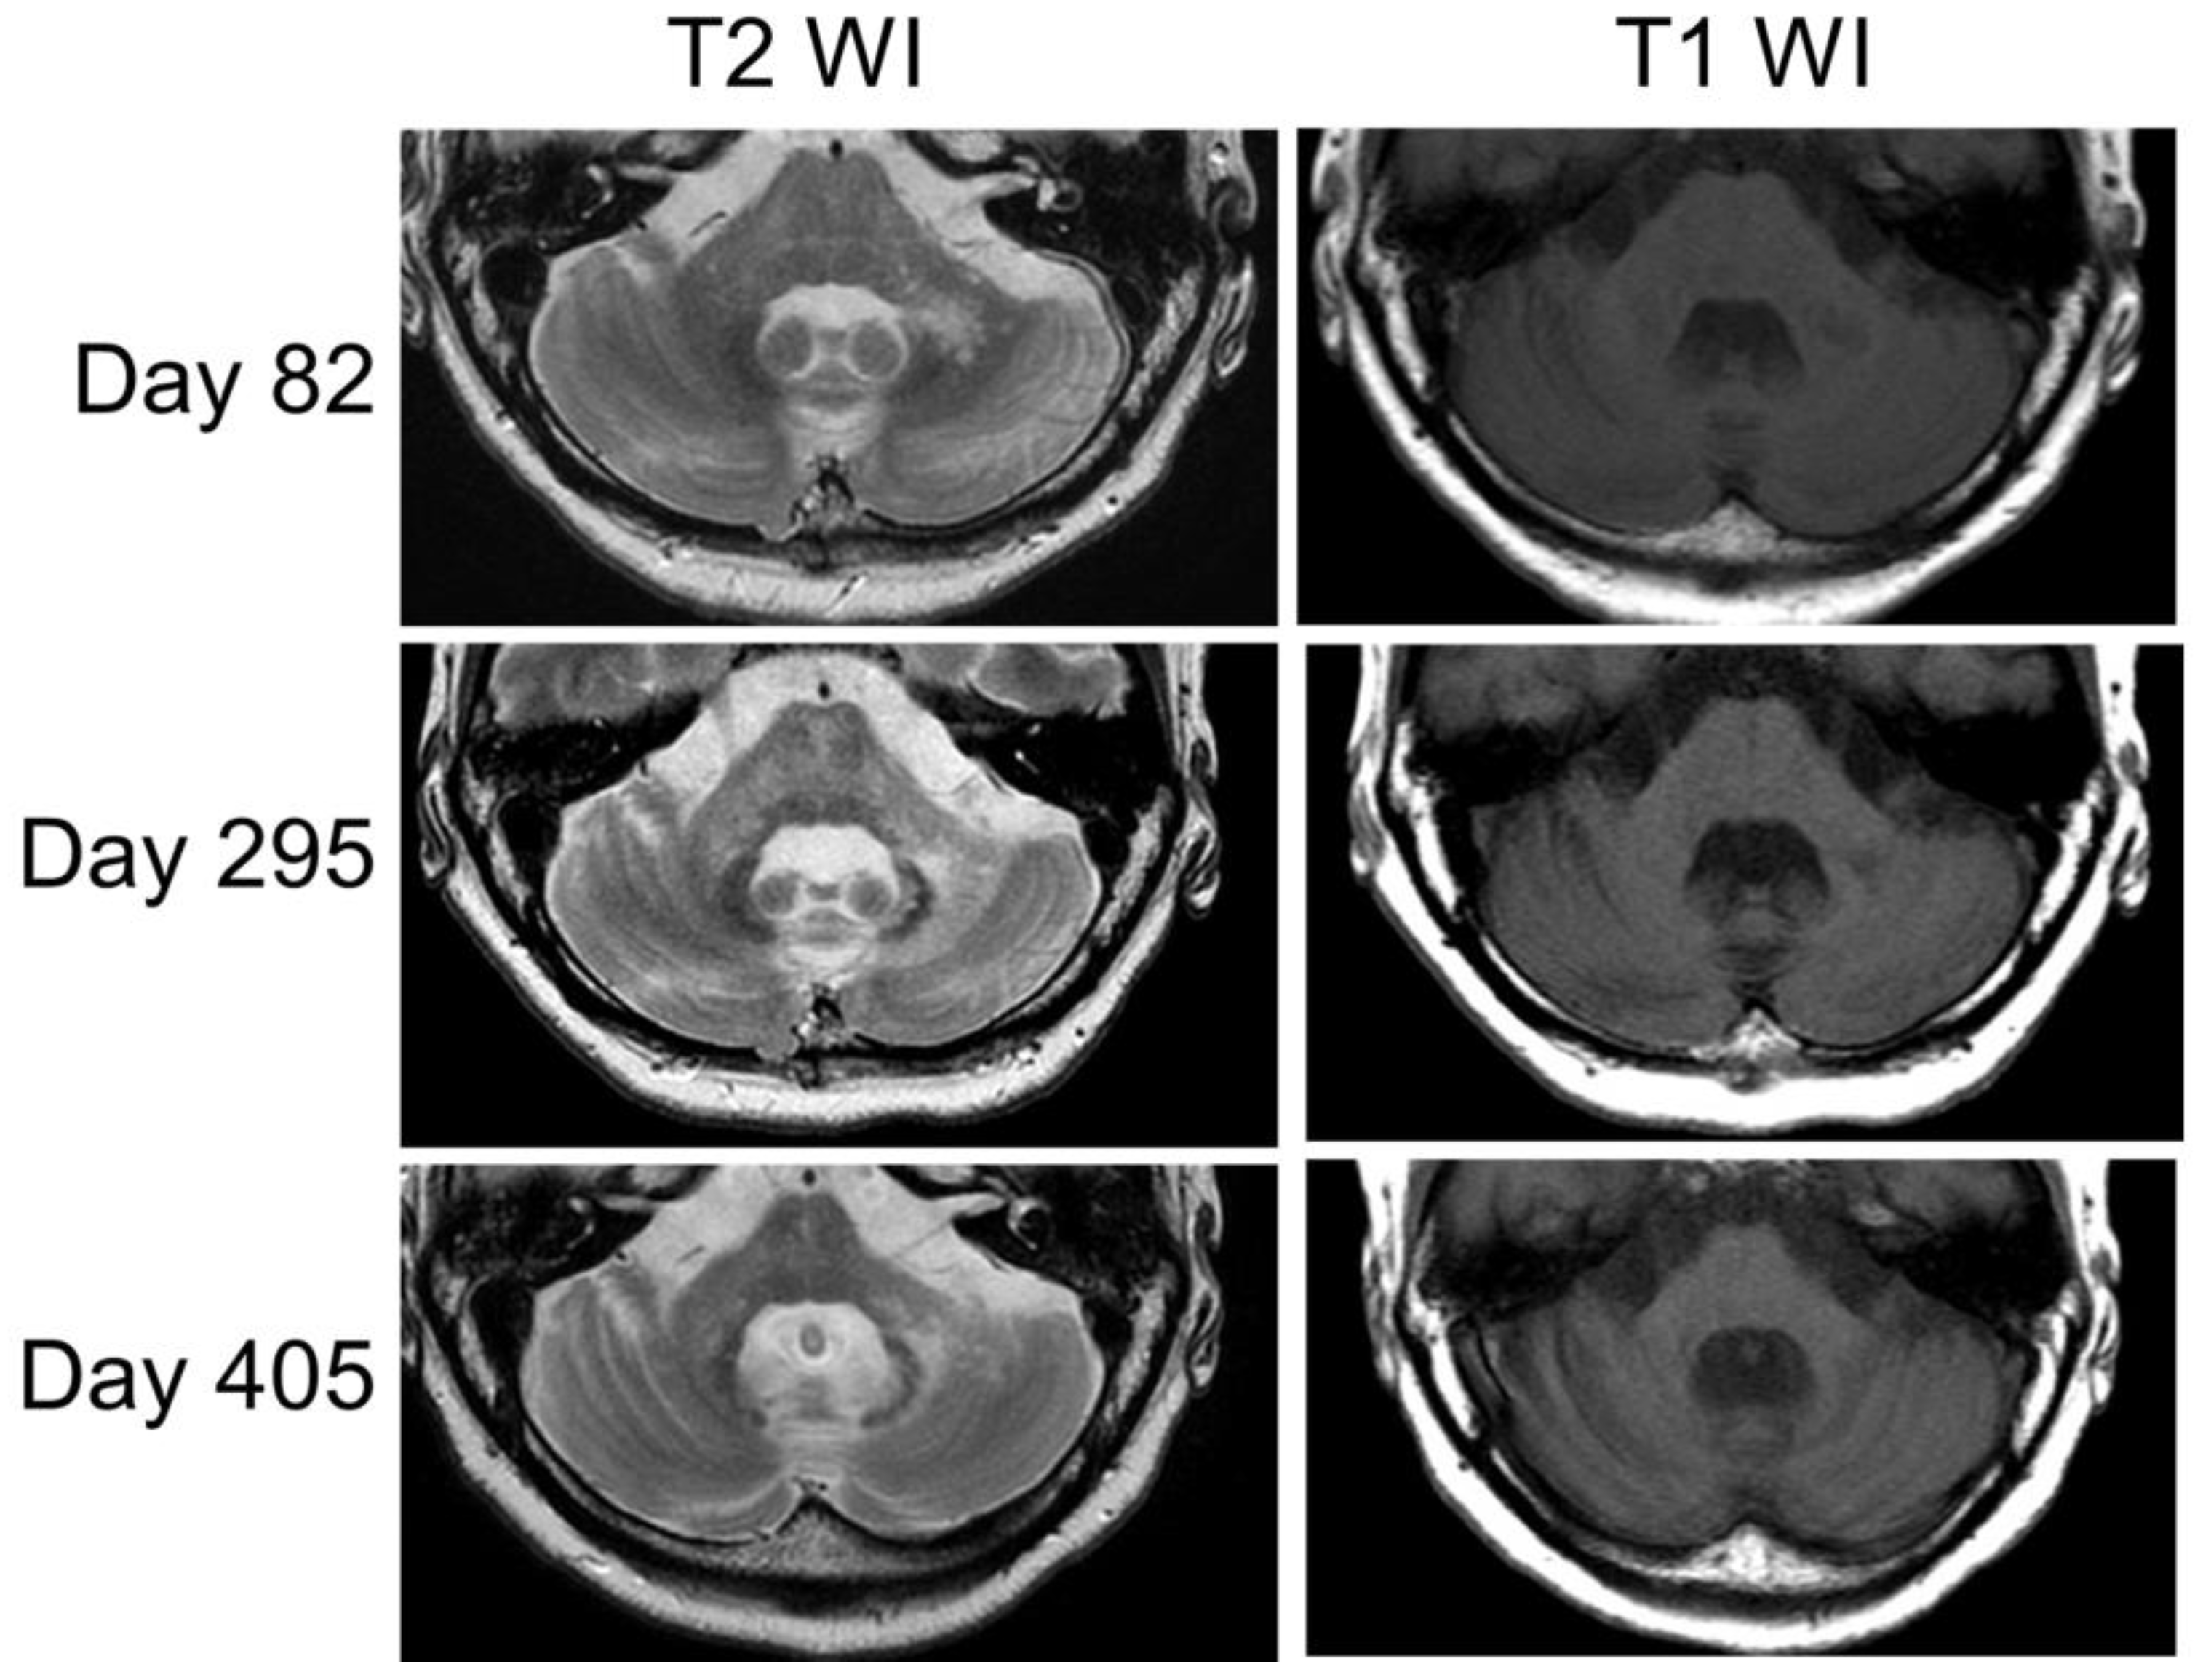

Akimoto, T.; Hara, M.; Hirose, S.; Nakamichi, K.; Nakajima, H. Cerebellar Progressive Multifocal Leukoencephalopathy Mimicking Anti-Yo-Antibody-Associated Rapidly Progressive Cerebellar Syndrome. Neurol. Int. 2023, 15, 917-925. https://doi.org/10.3390/neurolint15030059